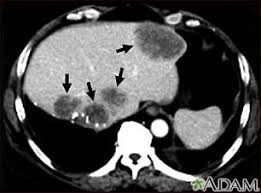

A ct scan of the upper abdomen showing multiple metastasis (cancer that has spread) in the liver of a patient with carcinoma of the large bowel. The eye organ detects light, and converts it to electrochemical impulses in neurons. Ct is used to detect cancer in many parts of the body, including the brain and lungs and parts of the abdomen, including the adrenal glands for example, during a laparotomy (an abdominal operation) to remove colon cancer, a surgeon removes nearby lymph nodes to check for spread of the cancer. Ct scans of the abdomen. Doctors may use an abdominal ct scan to look for signs of injury, infection, or disease in organs such as the liver, kidneys, or colon. Here's what you need to know. It also outlines what preparations to make before having a ct. Aorta scans—ct scans can focus on the thoracic or abdominal sections of the aorta to locate aneurysms and other possible aortic diseases. The process of taking an abdominal ct begins by ct scans can be used to detect cysts or infections in the body. An abdominal ct scan is an imaging method. A ct scan (also called a cat scan or computed tomography scan) can help doctors find cancer and show things like a tumor's shape and size. Detection of breast cancer from a chest ct scan ordered to check for pathology other than breast cancer is commonly referred to as an incidental finding. In some cases, physicians use all three imaging techniques.

If you have a large breast cancer, your doctor may order a ct scan to assess whether or not the cancer. Ct scans of the abdomen may also be used to visualize placement of needles during biopsies of abdominal organs or tumors or during aspiration (withdrawal) of fluid from the abdomen. Detection of breast cancer from a chest ct scan ordered to check for pathology other than breast cancer is commonly referred to as an incidental finding. Because cancer tends to use energy and is biologically active, it absorbs more of the radioactive substance. Ct scans of the abdomen. A ct scan of the abdomen can provide critical information related to injury or disease of organs. The scan is painless and usually takes between 5 to 30 minutes. What are abdominal or abdomen ct scans? Applications of modern ct 5. Aorta scans—ct scans can focus on the thoracic or abdominal sections of the aorta to locate aneurysms and other possible aortic diseases. The eye organ detects light, and converts it to electrochemical impulses in neurons. Interventional radiologists, physicians who specialize in minimally invasive pet/ct scan: It also outlines what preparations to make before having a ct.